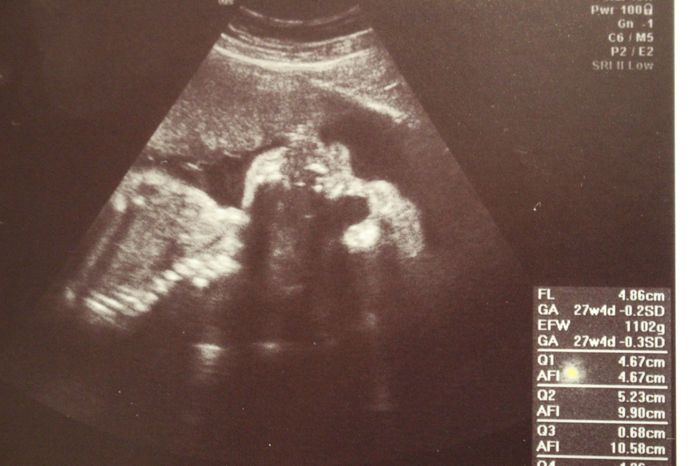

妊娠30週目のエコー写真

口をキュッとつぐむ様子も愛おしい表情。この頃は便秘がひどく、「酸化マグネシウム」を医師に処方してもらいました。この頃は安静にしながらも、週に1回催される母親学級へ車椅子で通い勉強していました。